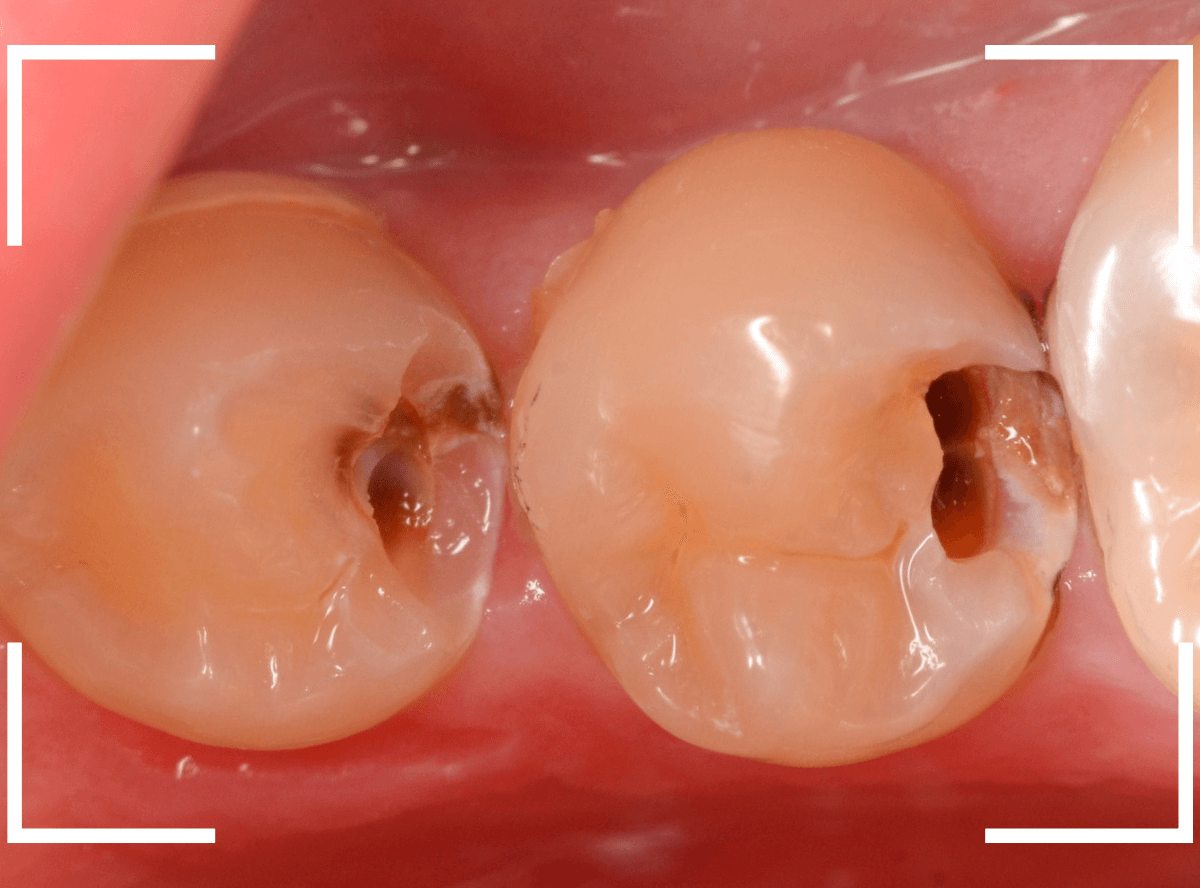

Case.21 神経に達しそうな2本の大きな虫歯

上の小臼歯の側面が明らかに虫歯になっている患者さんです。

患者さんは特に症状を感じてなさそうですが、恐らくは中で大きな虫歯になっているでしょう。

このように、自覚症状からだけでは虫歯の状況は診できません。

レントゲン写真で確認します。

青い線が歯の神経、赤い線が虫歯と思われる部分です。

2本とも、神経に達してしまいそうな大きな虫歯であると思われます。